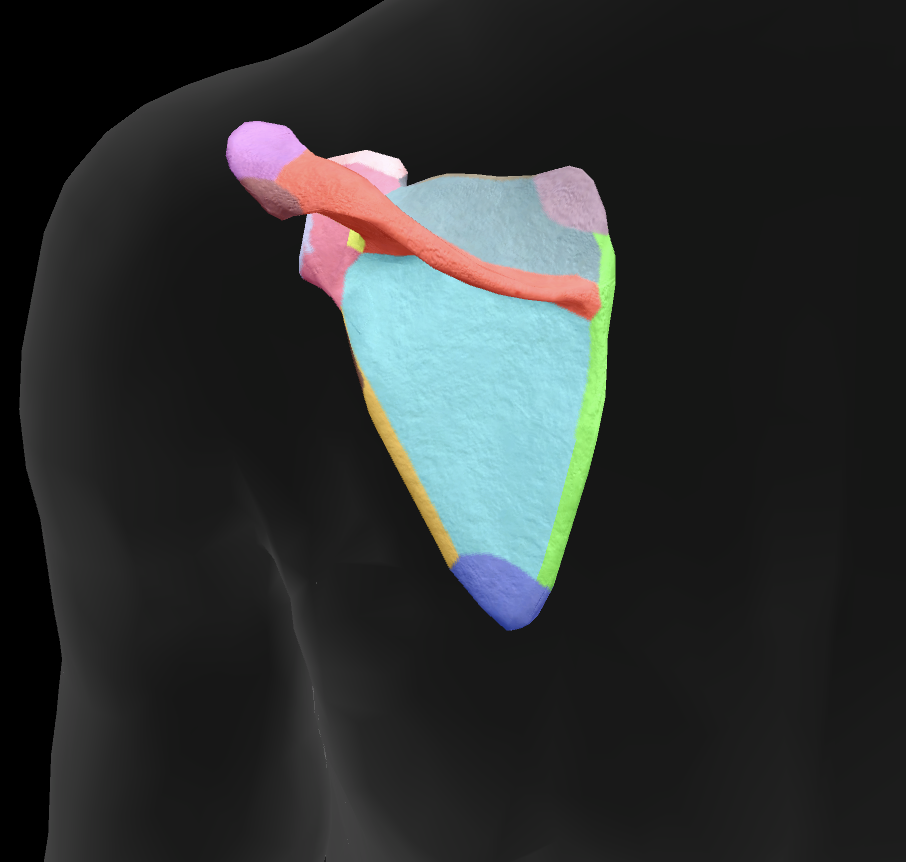

scapula

What is this boney landmark?

spine of scapula

What is this boney landmark?

supraspinous fossa

What is this boney landmark?

infraspinous fossa

What is this boney landmark?

acromion process

What is this boney landmark?

superior angle

What is this boney landmark?

inferior angle

What is this boney landmark?

lateral border

What is this boney landmark?

medial border

What is this boney landmark?

subscapular fossa

What is this boney landmark?

spinoglenoid notch

What is this boney landmark?

glenoid fossa

What is this boney landmark?

supraglenoid tubercle

What is this boney landmark?

infraglenoid tubercle

What is this boney landmark?

coracoid process

What muscle is this?

subscapularis

What muscle is this?

supraspinatus

What muscle is this?

infraspinatus

What muscle is this?

teres minor

What are the rotator cuff muscles?

supraspinatus, infraspinatus, teres minor, subscapularis